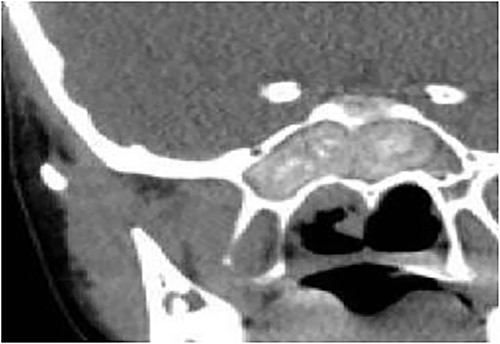

A 14-year-old male presented with a history of bilateral nasal obstruction for 3 years associated with snoring and postnasal discharge. Endoscopic examination showed bilateral nasal polyposis. CT scan of the paranasal sinuses (Fig. 3) & FESS, via which the sinuses were found full of polyps, mucin and fungal debris, confirmed the diagnosis of bilateral AFS. The patient continued on postoperative medical treatment and remained symptoms-free for 2 years follow-up.

Axial CT paranasal sinuses shows heterogeneous opacities filling the ethmoid and sphenoid sinuses bilaterally with hyperdense contents. The ethmoid sinus shows expansion with partial dehiscence of the right lamina papyracea.